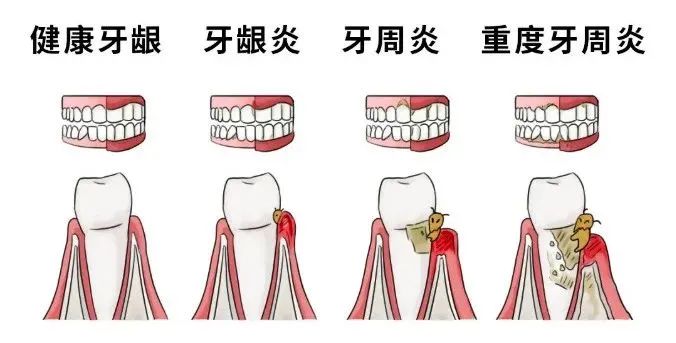

口腔疾病:如牙龈炎、牙周炎。牙结石堆积在牙龈周围,牙龈红肿,刷牙的时候就特别容易出血。

牙结石又称牙石,通常存在于唾液腺开口处的牙齿表面。如下颚前牙的舌侧表面,上颚后牙的颊侧表面和牙齿的颈部,以及口腔黏膜运动不到的牙齿表面等处。牙结石开始是乳白色的软垢,会因逐渐的钙化而变硬。它是由75%的磷酸钙,15%~25%的水、有机物、磷酸锰、碳酸钙及微量的钾、钠、铁所构成,并呈现出黄色、棕色、或者黑色。牙结石是牙周病发展的一个重要致病因素,如果不养成良好的口腔卫生习惯,即使彻底洁治后,牙结石很容易很快再次沉积在牙齿表面。